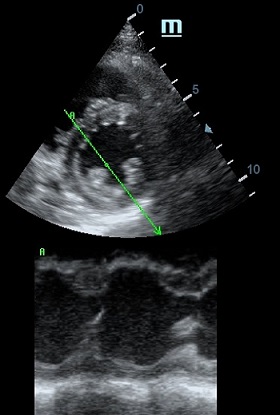

MAPSE - амплитуда движения латерального кольца митрального клапана, позволяет рассчитать фракцию выброса по формуле EF = 4.8 × MAPSE (mm) + 5.8, очень быстрый и гораздо более точный («прародитель Strain») метод чем широко распространенный метод Teicholtz. В современных приборах можно легко добавить свою формулу при отсутствии ее в стандартном калькуляторе. Главным условием является проведение линии М-режима параллельно стенке левого желудочка в апикальном четырехкамерном сечении, что легко достигается при использовании функции Free Xros.